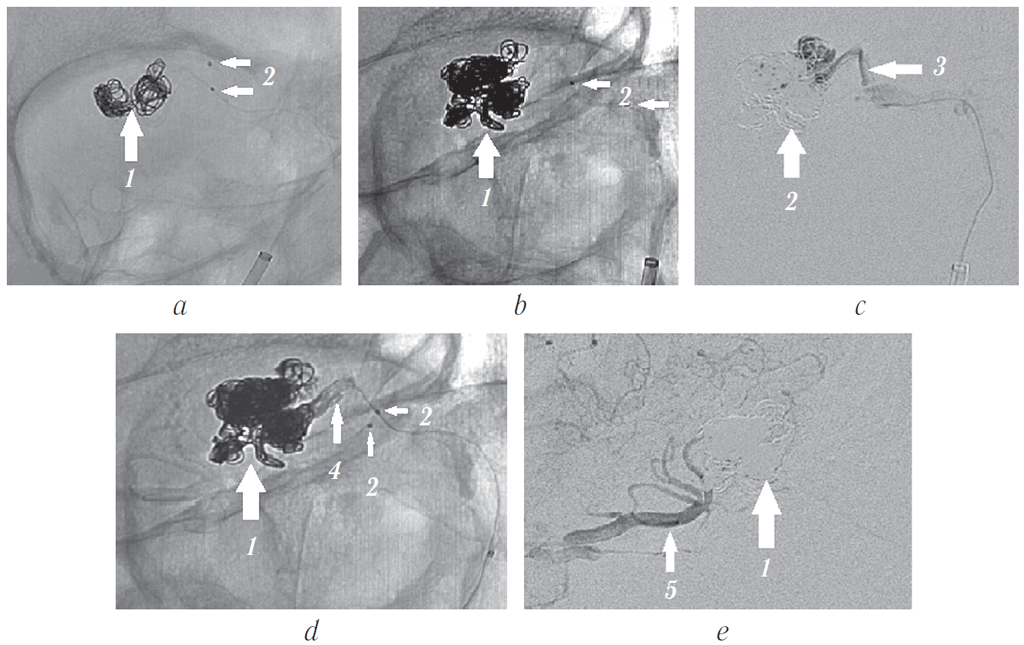

Под этапным ангиографическим контролем в сосудистую сеть опухоли введено и имплантировано 11 отделяемых микроспиралей Target.

Для достижения радикальности эмболизации, прекращения потока по дренирующей вене через микрокатетер введена жидкая клеевая композиция ONYX18. При контрольной ангиографии контрастирования сосудистой сети опухоли не наблюдалось (рис. 15).

Рис. 15. Динамика эмболизации сосудистой сети опухоли отделяемыми микроспиралями и результаты ангиографии: а и b — динамика эмболизации сосудистой сети опухоли; с — этапная ангиография через трансвенозный микрокатетер; d — конечный результат после введения жидкой неадгезивной клеевой композиции ONYX18; е — контрольная ангиография, конечный результат — собственная сосудистая сеть не контрастируется, дренирующая вена не заполняется. 1 — клубок микроспиралей Target, 2 — метки микрокатетеров, 3 — замедление кровотока по дренирующей вене, 4 — жидкая неадгезивная клеевая композиция в дренирующей вене, 5 — глазная артерия

Fig. 15. Dynamics of tumor vascular network embolization by detachable microspirals, and the results of angiography: a and b – dynamics of embolization of the vascular network of the tumor; c – phased angiography through a transvenous microcatheter; d – final result after the injection of the liquid non-adhesive composition ONYX18; e – control angiography, the final result – proper vascular network is not contrasted, the draining vein is not filled. 1 – Target coils, 2 – microcatheter tags, 3 – slowed blood flow through the draining vein, 4 – liquid non-adhesive composition ONYX18 in the draining vein, 5 – ophthalmic artery

При контрольной ангиографии (рис. 16, 17, b) отмечено отсутствие контраста в сосудистой сети опухоли с выраженным замедлением тока крови по дренирующей вене и приводящей ветви глазной артерии. Церебральные ветви проходимы, диаметр и топография их сохранены.